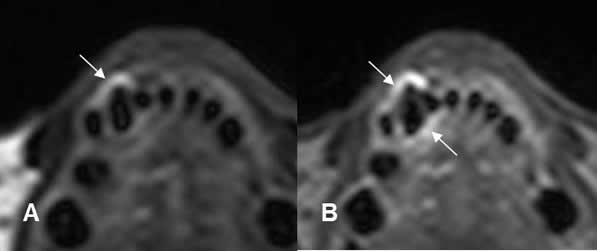

Fig 43. Enfermedad periodontal.

A: TAC axial y B: TAC reconstrucción sagital. Aumento del espacio periapical, por enfermedad periodontal.